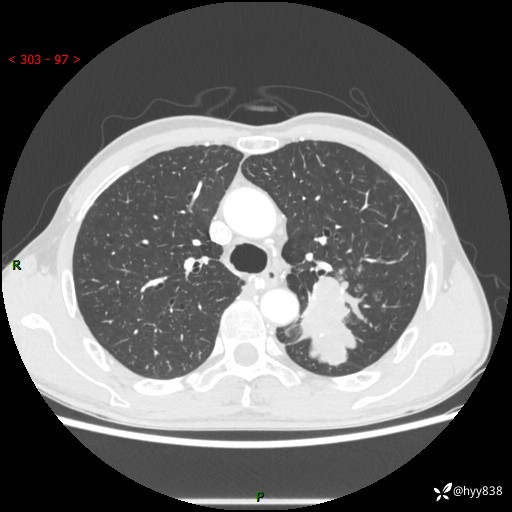

老年男性,咳嗽咳痰伴痰中带血4月。沿支气管铸形生长的不多---结果公布~

现病史:患者余4月前发现咳嗽咳痰伴痰中带血,无胸闷、胸痛、头晕、恶心、呕吐等不适,2天前因体检发现肺部结节遂于当地市第一人民医院行胸部CT薄层平扫+三维重建示:1.左肺上叶尖后段占位性病变考虑肿瘤性病变伴阻塞性肺炎,右肺上叶后段磨玻璃结节。2.肝内多发囊性灶、左肾结石。现患者为求进一步治疗,于我院门诊就诊,门诊以“肺结节”收入院。 自患病以来,精神、饮食、睡眠尚可,大小便正常,体力体重无明显减轻。

胸部CT增强扫描(外院平扫)